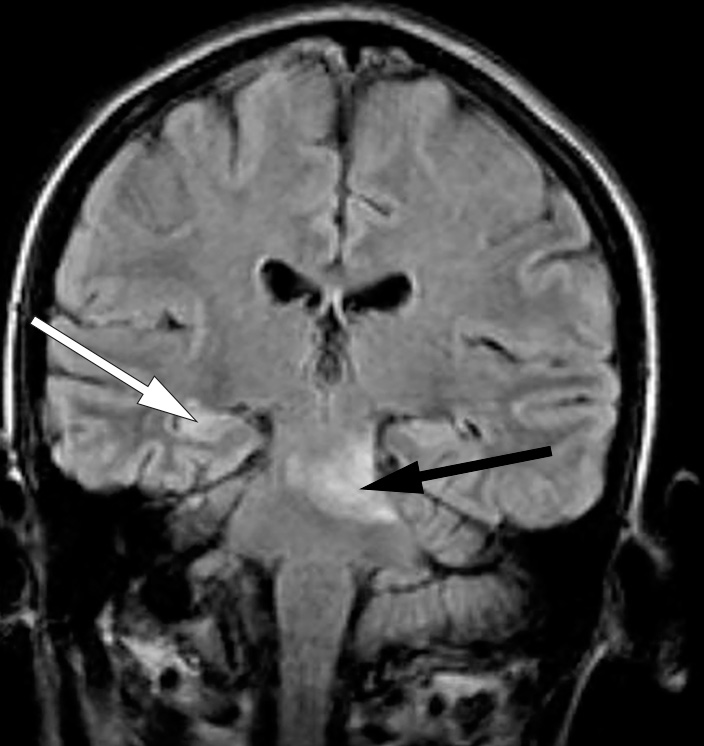

Pasientens visus ble imidlertid betydelig svekket. Øyelege fant okkluderte blodkar både på arterie- og venesiden samt blødninger i fundus (fig 4).

Slike vaskulittforandringer i øyebunnen ga mistanke om Behçets sykdom. Denne diagnosen var også vurdert tidlig i forløpet, men orale ulcerasjoner, som er vanlig ved denne tilstanden, var ikke observert under innleggelsene. Imidlertid kan potent immunsuppressiv behandling ha maskert slimhinnesår. På spørsmål om dette kom det frem at pasienten hadde vært plaget med residiverende orale ulcerasjoner i mange år. Tilstanden ble oppfattet som Behçets sykdom med affeksjon av øyne og sentralnervesystemet. Det var tilkommet en sikker bedring av de sentralnervøse manifestasjonene, men på grunn av økende vaskulittforandringer i øyebunnen begynte man tre måneder etter siste rituximabinfusjon med infliksimab 3 mg/kg etter behandlingsprotokoll for revmatoid artritt. Pasientens sykdomsbilde har holdt seg stabilt etter oppstart med infliksimab.